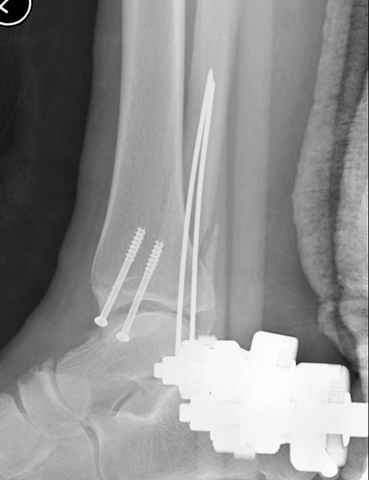

Еще, кстати, о фиксации лодыжки, если уж непременно хочется ее отдельно стабилизировать - при таком характере перелома замечательно должен сработать предложенный проф. Лазаревым с соратниками способ фиксации напряженной V-образной спицей. Опять же, открытая репозиция не нужна, мы делаем непрямую репозицию именно аппаратом. В приложении пример, там перелом малоберцовой куда менее поперечный, чем в данном случае, но все равно получилось закрыто без пластинки.

A propos fibular fixation if one is eager to stabilize it separately. In the fracture pattern a way of closed fixation by V-shaped stressed wire (advanced by colleagues from Moscow, prof. Lazarev A.F. et al.) must be excellent. We use indirect closed reduction by the external fixator. Example attached, that fibular fracture is even more suitable for plating but the wire did the job.